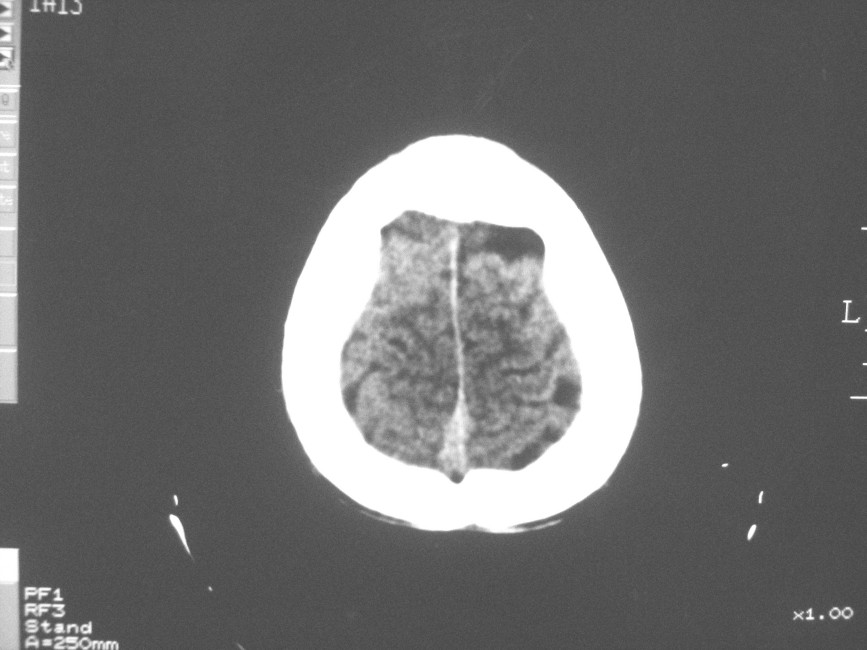

以下是引用zzyy在2008-6-16 10:13:00的发言:[br]两侧脑白质呈对称性密度减低,病儿有发热及脑膜刺激征。考虑急性病毒性脑炎。